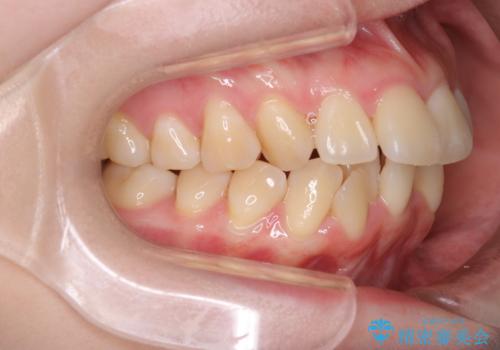

- 前歯が出ていることと、下の歯のがたがたで歯磨きがしにくいことを主訴に来院されました。

マウスピース矯正の希望があり、ワイヤーリカバリの可能性を伝えたうえでインビザライン抜歯矯正を行っています。

来院が途中途絶えたこともあり、4年ぐらい期間がかかりましたが、インビザラインだけで治療を終えることができました。